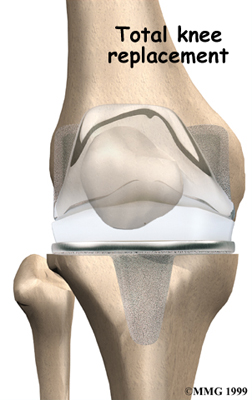

Artificial Knee Replacement

An artificial knee replacement is the ultimate solution for advanced knee OA.

Surgeons prefer not to put a new knee joint in patients younger than 60. This is because younger patients are generally more active and might put too much stress on the joint, causing it to loosen or even crack. A revision surgery to replace a damaged prosthesis is harder to do, has more possible complications, and is usually less successful than a first-time joint replacement surgery.

Related Document: FYZICAL Camilla's Guide to Artificial Joint Replacement of the Knee